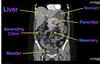

label this CT

Label the: * liver * gall bladder * ascending colon * bladder

label the: * Kidney * Aorta * Stomach * Liver * IVC * Aorta